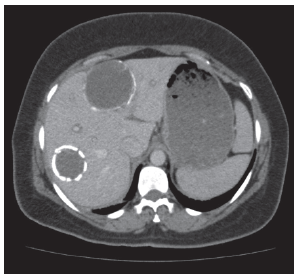

A 38-year-old Iraqi woman with known hydatid cysts presented to the emergency department with a 2-week history of worsening malaise, nausea, fatigue, and jaundice. Echinococcus was established 3 months prior, while during work-up for abdominal pain, and ultrasound revealed 2 hydatid cysts measuring 7.4 cm × 6.7 cm and 6.7 cm × 5.2 cm (Figure 1 and Figure 2). Laboratory studies indicated positive echinococcus IgG enzyme-linked immuno­sorbent assay with confirmatory Western blot. The patient was initiated on albendazole 400 mg twice daily and remained well for a month before her presentation to our facility. On presentation, she was found to have abnormal chemistries with elevated aspartate aminotransferase (AST) 1705 IU/L, alanine aminotransferase (ALT) 2118 IU/L, total bilirubin 5.0 mg/dL, and international normalized ratio 1.3. An examination revealed jaundice and scleral icterus, with no asterixis and normal mentation. She was admitted for expedited work-up of acute liver injury and albendazole was discontinued.